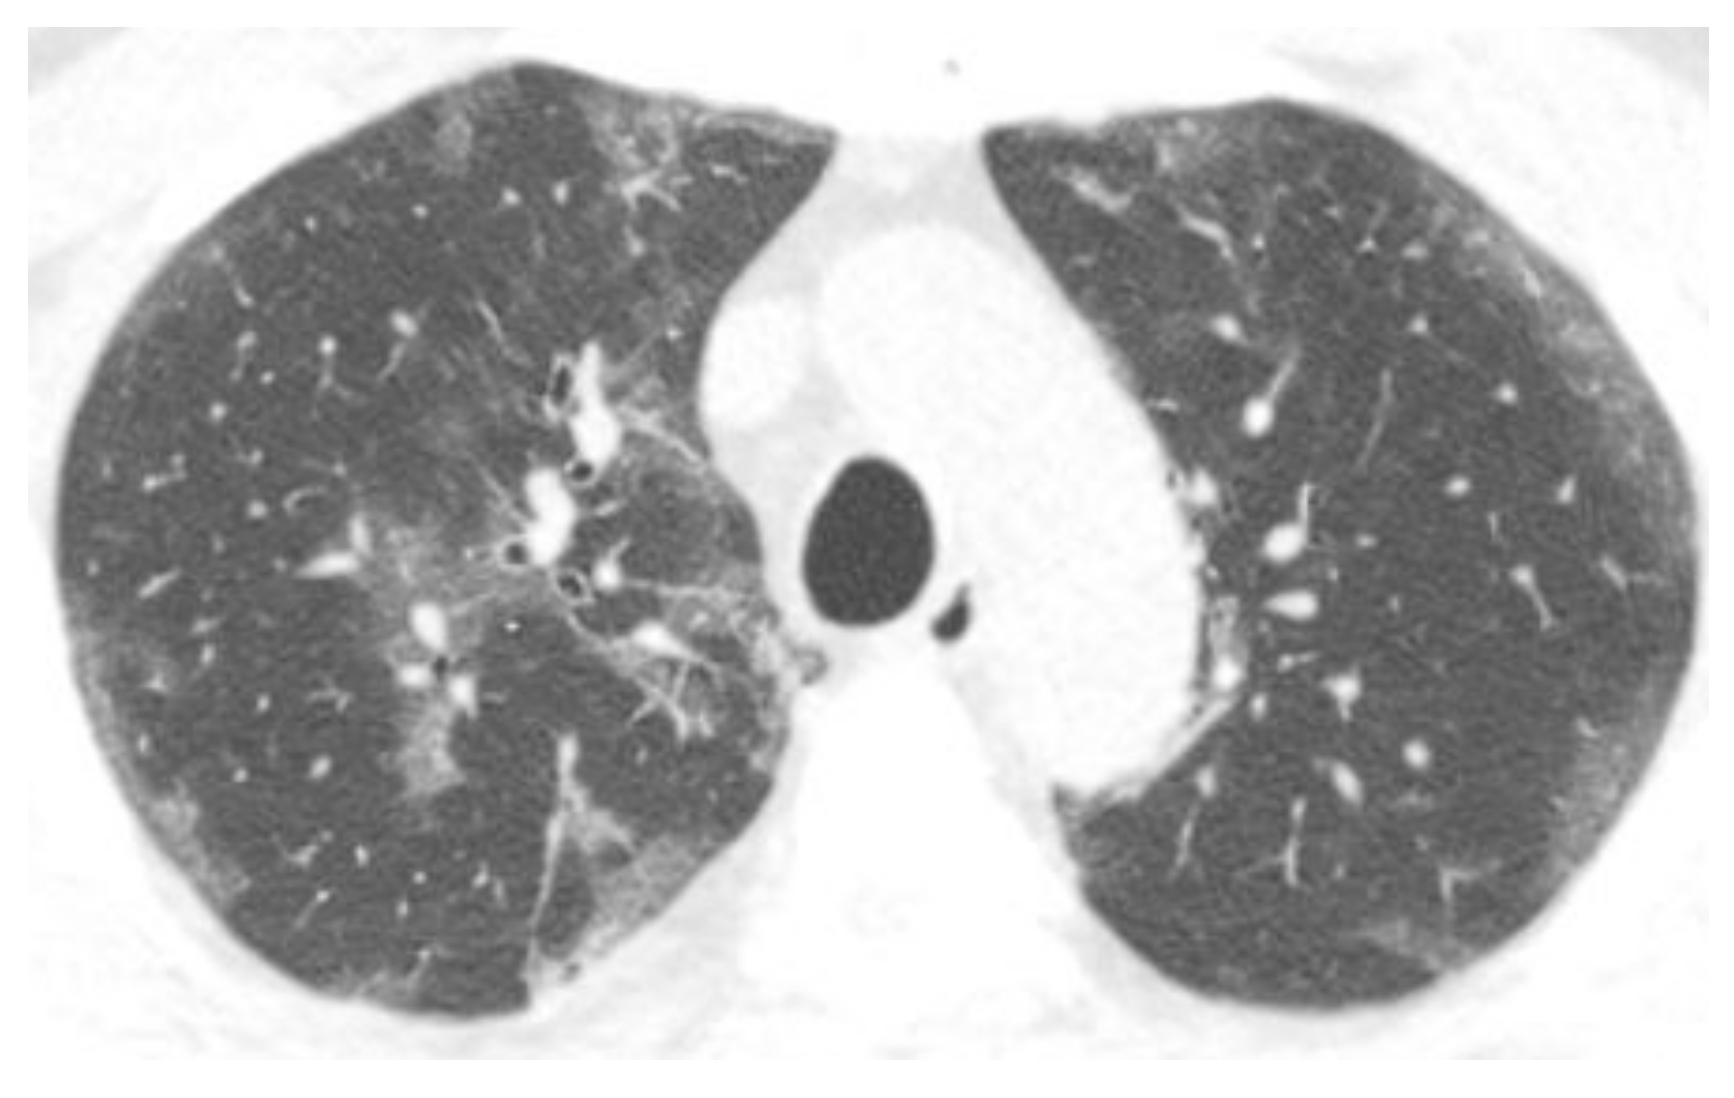

3.2. Chest CT Scans Performed in the Acute Phase (0–4 Days)

3.3. Chest CT Scans Were Performed in the Subacute Phase (5–12 Days)